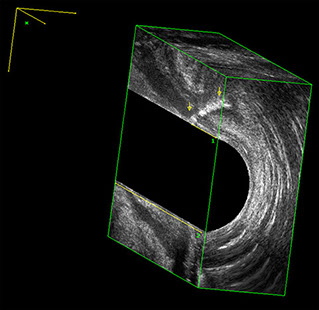

L’ecografia transanale è un esame diagnostico per immagini che consiste nell’introduzione di un trasduttore ad ultrasuoni. Le immagini qualitativamente migliori del canale anale sono ottenute usando un trasduttore rotante, montato in un manipolo rigido, che fornisce un’immagine a 360°. Con le apparecchiature più moderne è anche possibile ottenere immagini tridimensionali.

Proctal dispone di apparecchiatura per ecografia endoanale 3D con sonda rotante.